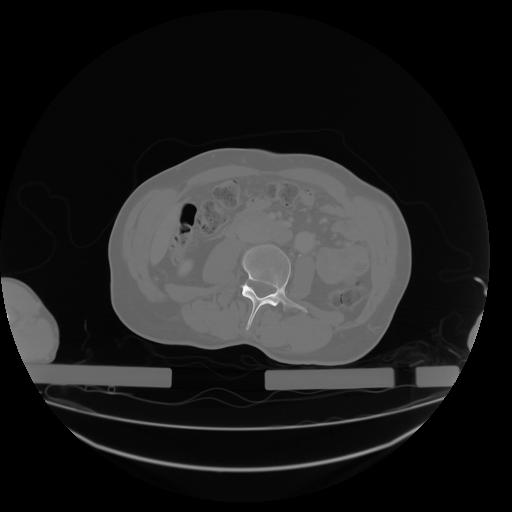

27 CUERPO,CE,Axial,3.0,CUERPO,,